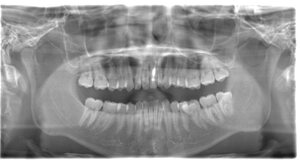

親知らずは真っ直ぐに生えていましたが一部歯ぐきが被っており、歯ブラシが上手くできず虫歯になり歯石もたくさん付いていました。

術中・術後痛み出血もほとんどなく、抜歯後は親知らずを抜いた事により歯磨きが楽になったと喜ばれていました。

治療前パノラマ

| 年齢・性別 | 40代・男性 |

|---|---|

| 主訴 | 親知らずが磨きにくいので抜きたい |

| 治療内容 | 右下親知らず通常抜歯 |

| 治療期間 | 約30分 |

| 治療費 | 合計約6,000円 約2,500円(保険診療3割負担) 別途CT撮影で約3,500円 (2022年12月現在) |

| リスク・副作用 | 下顎の歯は、骨の中を通っている血管、神経や舌の神経に近接しているため、術後に下唇や舌の知覚異常を起こす可能性があります。 |

| 治療方針 | 事前にCT撮影を行い神経との位置関係を確認して抜歯を行いました。 |